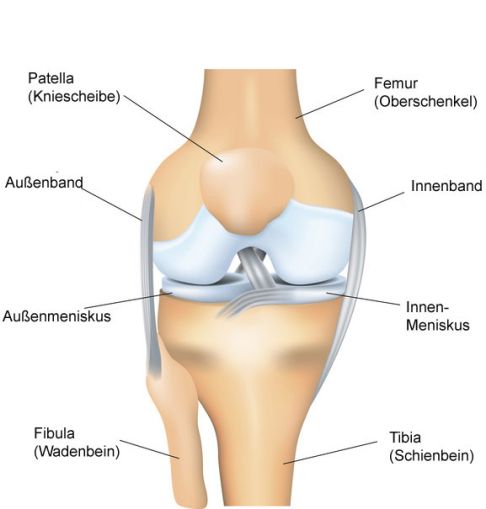

Anatomie des Kniegelenks von vorne gesehen: Auf dem verbreiterten Schienbeinplateau (Tibiaplateau) liegen die mächtigen rollenartigen Walzen des Oberschenkelknochens (Femurkondylen) als Gelenkpartner. An Osteochondrosis dissecans erkrankt vor allem der innen (medial) gelegene Femurkondylus. © ttsz, istockphoto